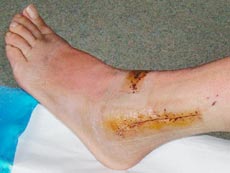

Für die nächsten sechs Wochen sind Rollstuhl und Krücken angesagt...